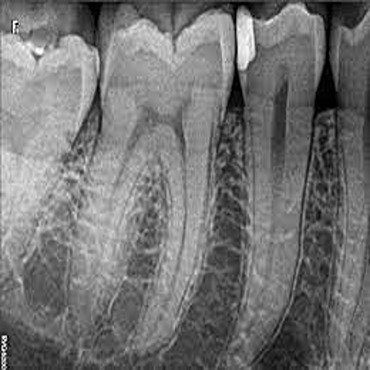

Shagun Dental Care in Lucknow offers a host of treatments and cures for a wide range of dental ailments faced by the patients. Few of the dental procedures they offer range from inducing fillings and repairs in the tooth, undertaking root canal surgeries, applying crowns (caps), bridges and implants, teeth whitening as well as extractions (surgical removal) of cavities/milky /disfigured/wisdom teeth.

I Had a wonderful and pleasant experience here. I got my single sitting RCT done here. Got the appointments according to my convenience and they also follow high standards of hygiene. The doctors here are very good and they addressed my queries and concerns in great detail. The entire process was painless and fast. Kudos to the team at Shagun Dental Care. I highly recommend them.